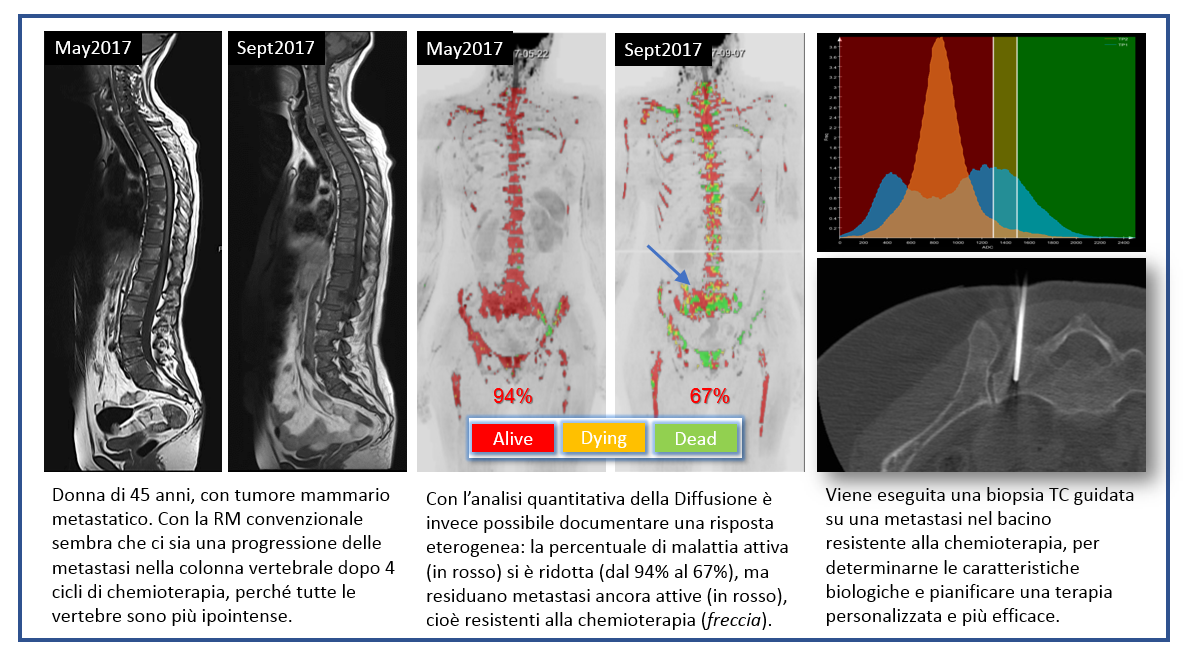

Le tecniche di imaging funzionale permettono di studiare non solo la morfologia delle lesioni tumorali, ma anche le loro caratteristiche funzionali, come ad esempio la densità cellulare, la perfusione e il metabolismo. L’integrazione dell’imaging funzionale con i parametri clinici e altri biomarcatori del singolo paziente prende il nome di “imaging di precisione”.

Grazie all’imaging di precisione è possibile valutare in maniera più accurata la presenza di un tumore, la sua estensione e l’efficacia delle terapie somministrate, allo scopo di rendere personalizzata la cura oncologica, in relazione alle esigenze del singolo paziente.

Imaging di precisione: caso 2